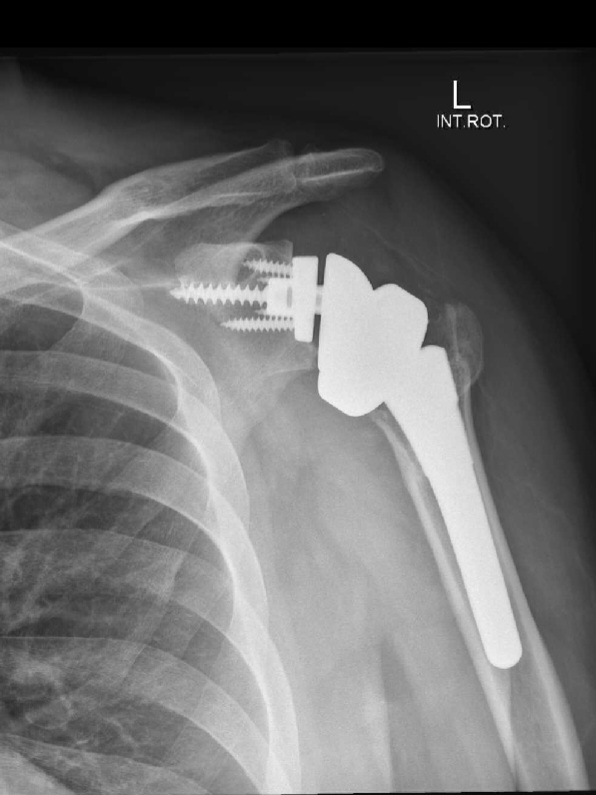

In late June 2024 I had a new shoulder installed; this is my three-month recovery diary.

Fabulous pictorial of your procedure 😊 Really glad it went well and you’re back on the bike.